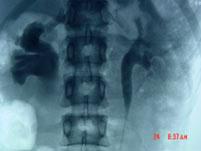

问题 男,20岁,右腰部胀痛不适,MR如图示,下列说法正确的是 ( )

选项 A、考虑为右侧腔静脉后输尿管 B、考虑为右侧输尿管自身的扭曲 C、右侧输尿管上段扩张积水 D、右侧输尿管走行异常,呈“S”形向中线移位 E、右侧肾盂积水

答案 ACDE